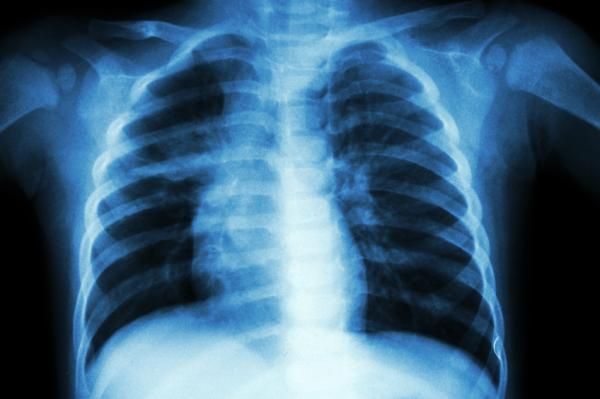

El diagnóstico por imágenes es una herramienta fundamental en la medicina moderna, permitiendo la evaluación precisa y no invasiva de diversas patologías. En el área del tórax, los avances tecnológicos han revolucionado la capacidad de los profesionales de la salud para detectar, diagnosticar y monitorizar enfermedades pulmonares y cardiacas. El Dr. José Luis Criales Cortés, un experto reconocido en este campo ha contribuido significativamente a estos avances, especialmente en el desarrollo y la aplicación de nuevas técnicas de imagen.

La tomografía computarizada (TC) de alta resolución ha sido una de las innovaciones más importantes en el diagnóstico por imágenes del tórax. Esta técnica permite obtener imágenes detalladas de los pulmones y otras estructuras torácicas con una resolución sin precedentes. El Dr. Criales Cortés ha sido pionero en el uso de TC de alta resolución para identificar y caracterizar enfermedades pulmonares intersticiales, tumores y anomalías vasculares con mayor precisión.

La TC de alta resolución es particularmente útil para detectar enfermedades pulmonares en etapas tempranas, lo que permite iniciar tratamientos oportunos y mejorar los pronósticos de los pacientes.